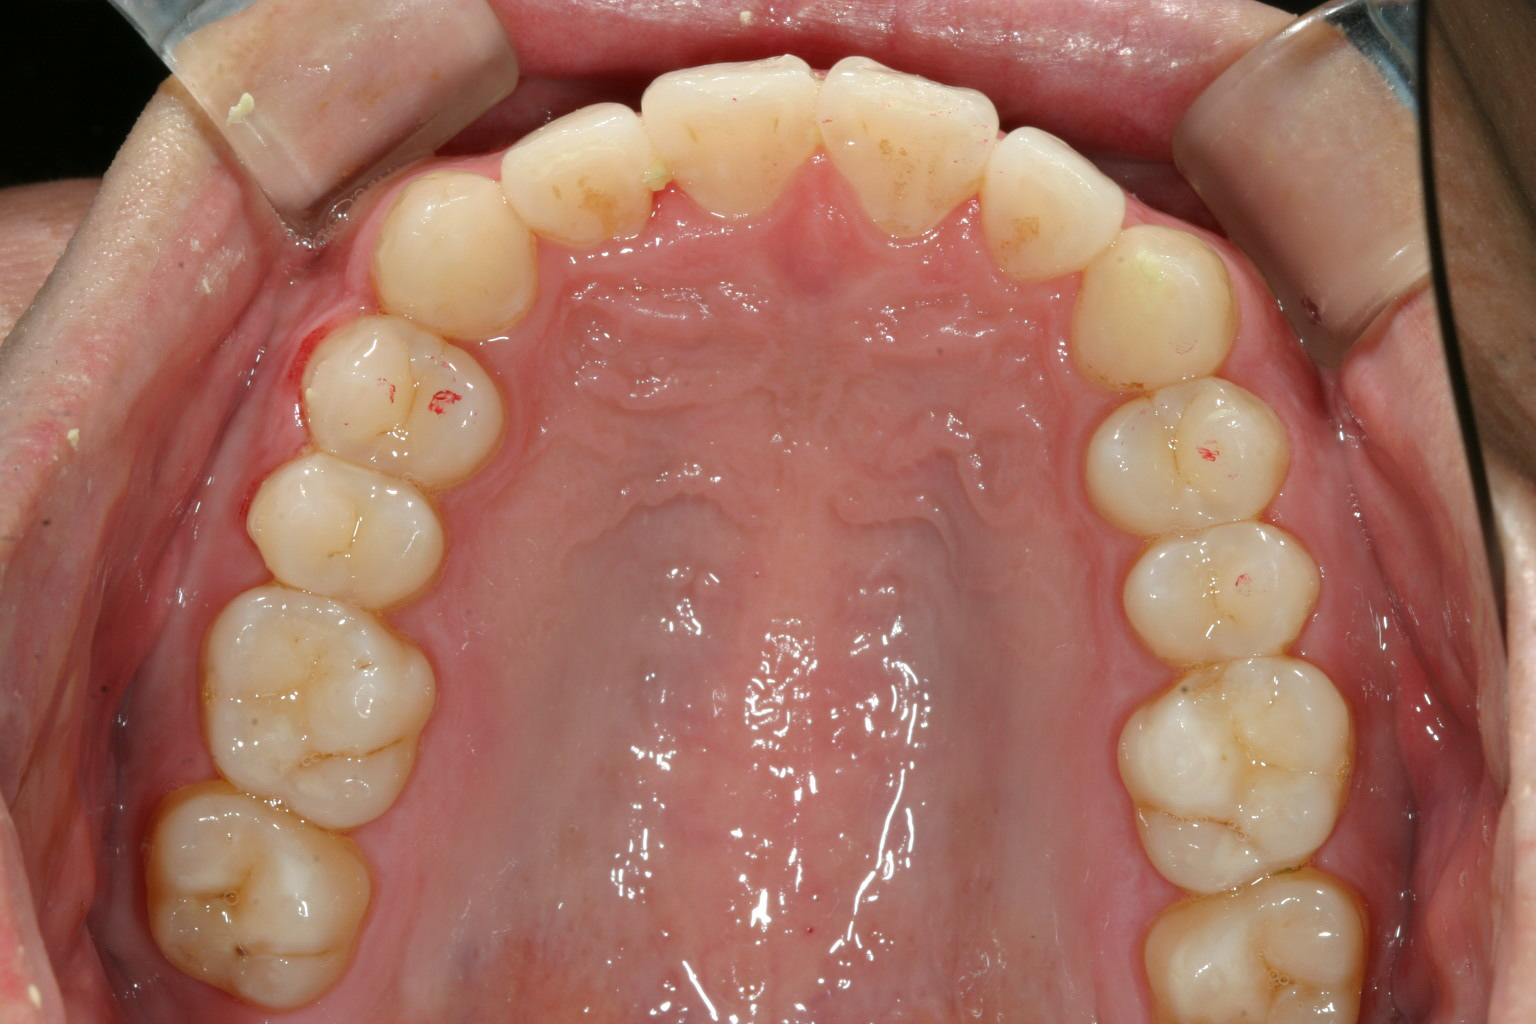

捻転も綺麗に改善です。

下顎も綺麗なアーチに改善しました。

前突感も有りません。